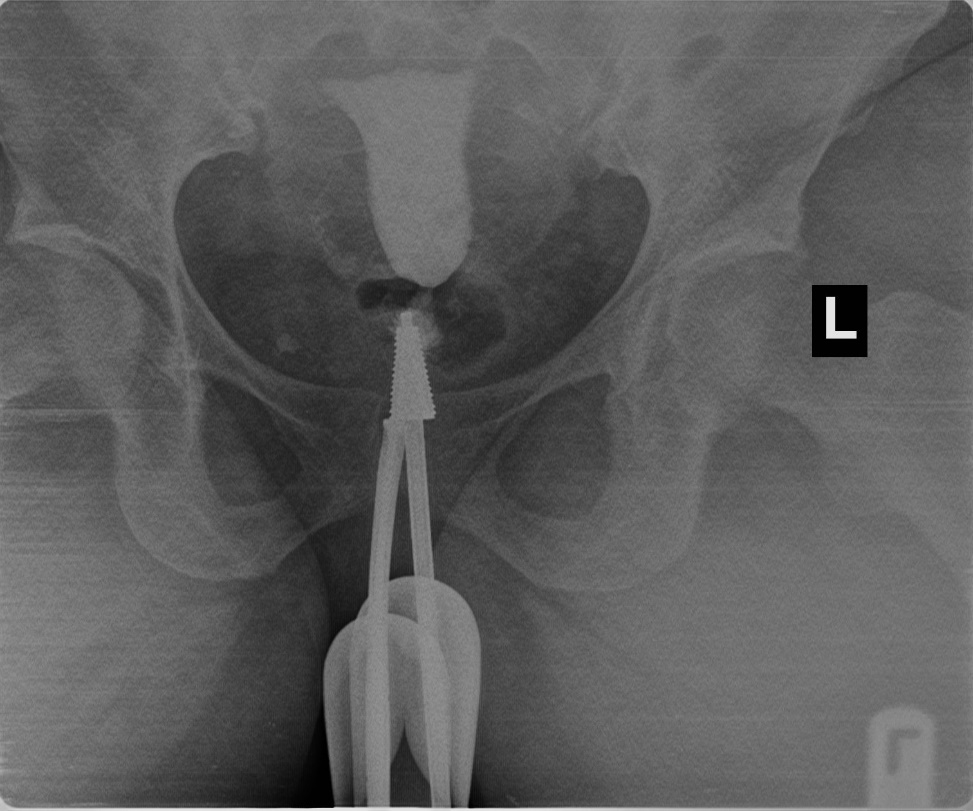

Figure 4: shows right proximal tubal occlusion

The prevalence of tubal pathologies in this study was 29.7% with bilateral proximal tubal occlusion being the most common abnormality, accounting for 10% of cases. This finding corroborates studies conducted in Lagos20 and Oghara21, where similar patterns were reported. However, a study in Zaria22 found unilateral tubal occlusion to be more common. Among unilateral cases, right sided blockages (5.7%) were more prevalent than left sided (2.6%), consistent with findings in Sokoto15 and Lagos20. Conversely, studies in Maiduguri16 and Korle-Bu14 reported left sided predominance. Some cases of bilateral proximal tubal occlusion were presumably due to tubal spasm; in this study all patients had intramuscular injection of hyoscine bromide (Buscopan) at the beginning of the procedure which is thought to prevent spastic tubal occlusion.